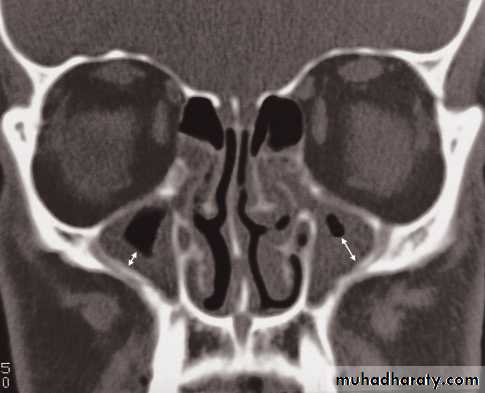

• However, CT is often the preferred technique in sinus disease

Blow out fracture

A direct blow to the eye raises the intraorbital pressure and can result in a fracture of the orbital floor, which is the weakest part of the orbit. The break in the orbital floor allows herniation of orbital contents into the antrum,Salivary glands